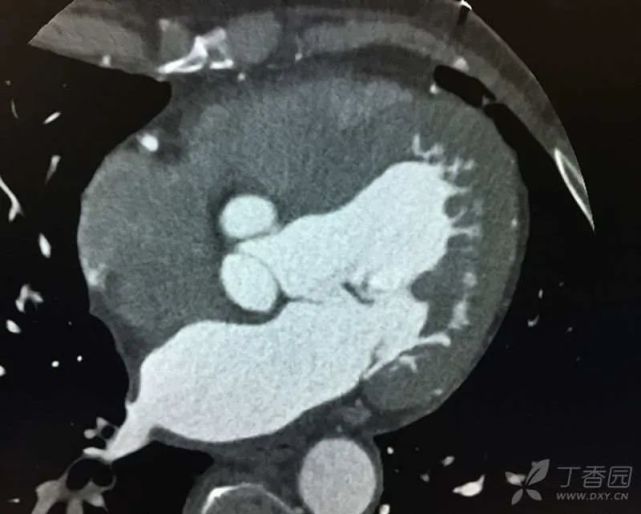

2012 年至 2015 年,患者 3 次因「活动后憋喘」入住我院心内科,诊断为:冠心病,慢性心功能不全(心功能II ~ II级)。住院期间查脑钠肽:9842 ~ 14835 pg/mL。心脏彩超结果显示:(1)室间隔、左室前壁运动幅度稍小;(2)左房增大,左室内径高界,二尖瓣少量返流;(3)主动脉稍增宽,主动脉瓣增厚伴少量返流;(4)左心功能测定:低界。冠脉 CTA:冠脉粥样硬化性改变,右冠远端、左冠前降支、对角支、回旋支轻度狭窄。心脏增大,左室为主(图3)。住院期间予地高辛、葛根素、螺内酯、氢氯噻嗪等对症治疗后。憋喘症状缓解,脑钠肽多可降至1000 pg/ml以下。

图片

(图 3 冠脉 CTA)